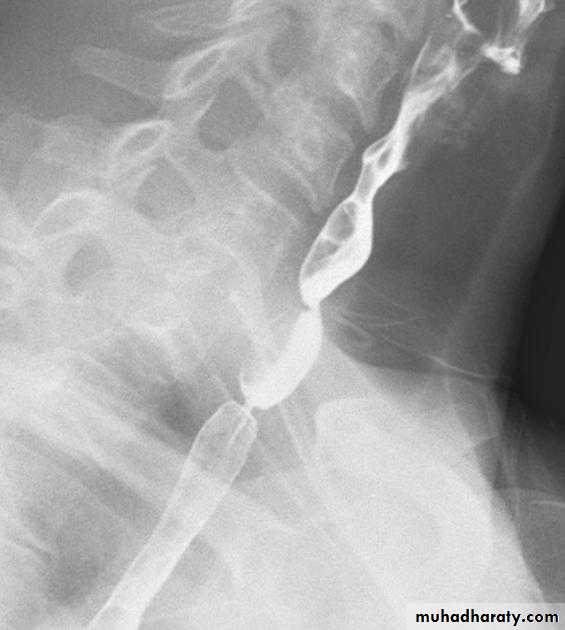

• 2. Dysphagia: post-cricoid esophageal webbing (Plummer Vinson syndrome).